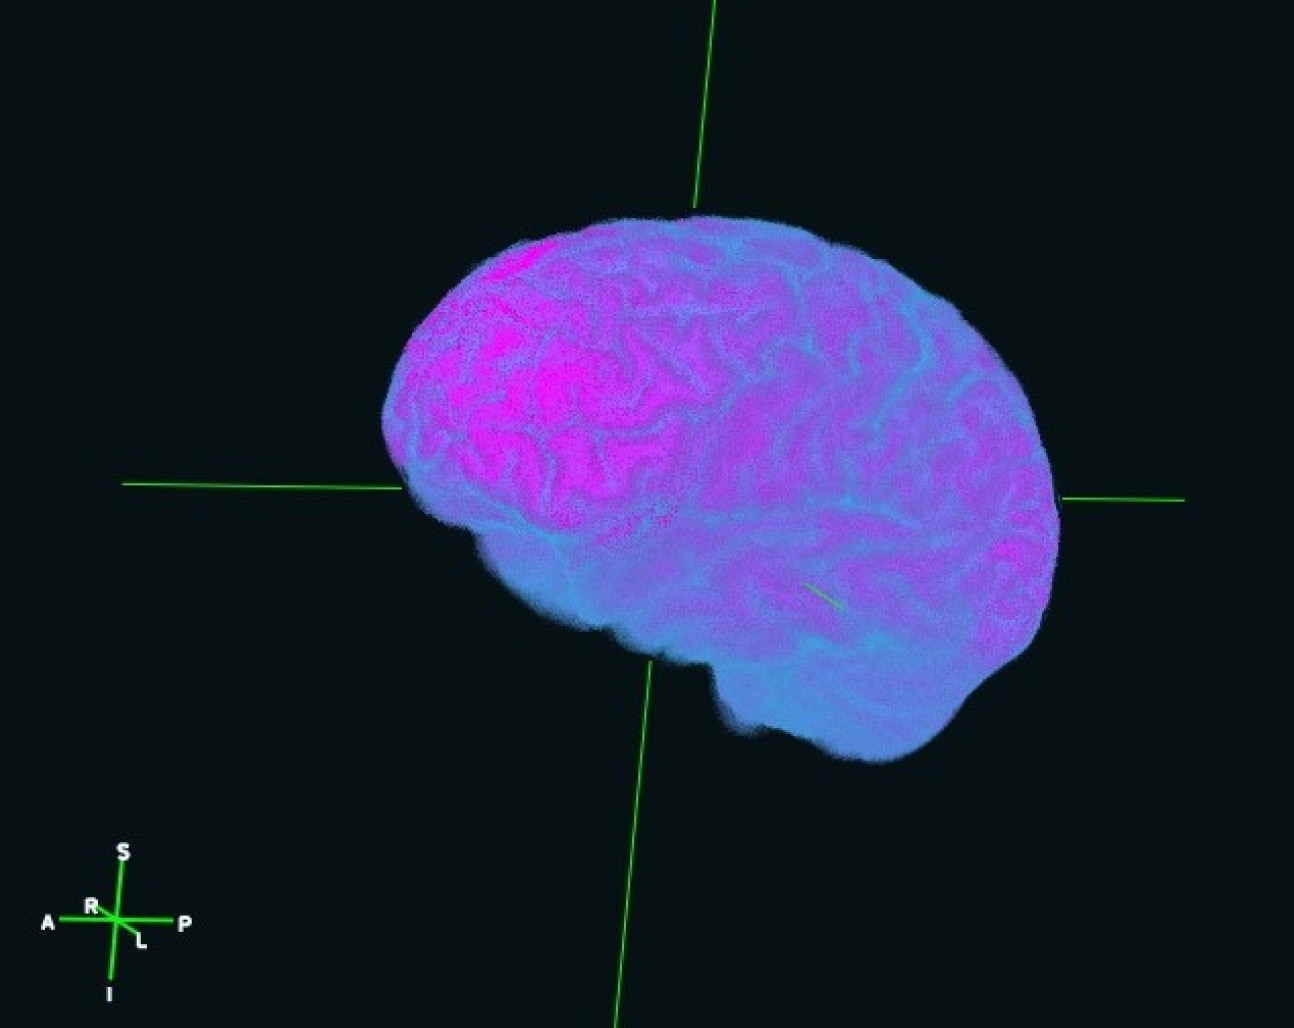

Neon Brain - Brian Schilder (PhD Student: Skene lab)

"3D surface reconstruction of the brain of the artist from 2D structural MRI scans, rendered with FreeSurfer."